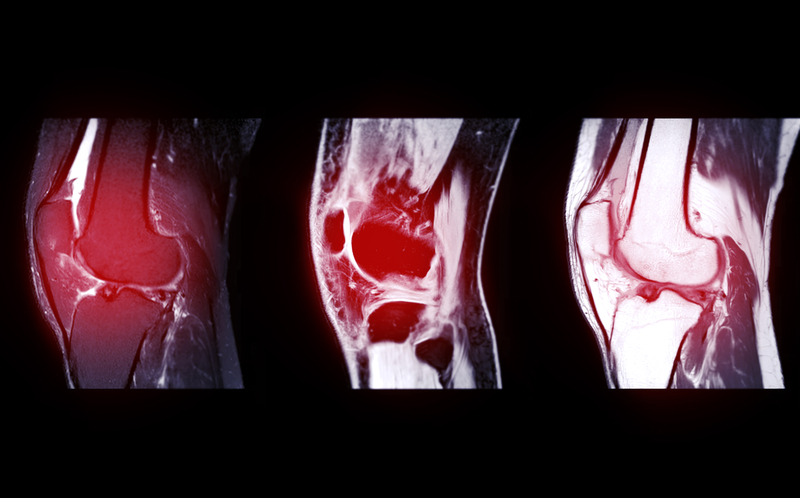

What’s more, they write in the article that “We focused on three common clinical conditions: uncomplicated lower back pain, nontraumatic knee pain without joint effusion, and nontraumatic shoulder pain without joint effusion. We selected these conditions for several reasons: They are prevalent among adults in the US, well-established guidelines exist for when imaging is appropriate, and imaging for the conditions is routinely performed in a variety of clinical settings.13,15 Thus, MRI referrals for these conditions are potentially valuable as tracers for broader changes in clinical practice that may be connected to the hospital employment of physicians. For the study sample, we excluded patients who had chronic comorbidities as well as clinical complications (for example, spinal stenosis) that might affect how a physician assesses the value of an MRI for diagnostic purposes. Patients included in the study sample thus were likely to be generally healthy outside of the relevant condition for which they sought medical care. We also excluded patients younger than age eighteen.”

As the authors note, “Organizational independence between hospitals and physicians has long been a defining feature of the US health care system but also arguably an impediment to better coordination of care for patients. At the same time, the growing trend among physicians toward hospital-based employment arrangements has raised concerns about possible negative effects on the cost, quality, and accessibility of patient care.” Indeed, according to the findings of their analysis, “Once employed by a hospital, physicians were more inclined to refer patients for MRI scans than before their employment.” Looking at MRI scan orders for uncomplicated lower back pain, nontraumatic knee pain without joint effusion, and nontraumatic shoulder pain without joint effusion, they found that “hospital employment was associated with a substantially greater likelihood of patients receiving MRI referrals in general, as well as—more important—inappropriate referrals. Once employed by a hospital, physicians were more inclined to refer patients for MRI scans than before their employment. Most of the patients that the hospital-employed physicians referred for MRI scans received those scans at the same hospital that employed the referring physician. Our findings offer evidence that such higher costs are not largely a matter of better service access for patients. Our findings are in line with previous studies that have reported an association between hospital-physician integration and higher costs for patient care,” they write. “However, our findings offer evidence that such higher costs are not largely a matter of better service access for patients. Rather, hospital-physician integration appears to be a potential driver of low-value care.”